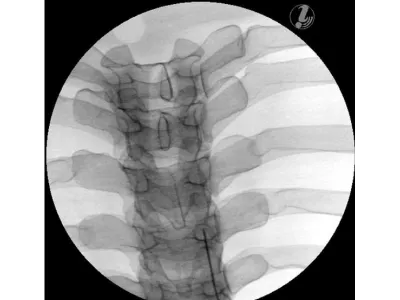

Тренажер для спинальных инъекций в грудную клетку под визуальным контролем

Тренажер для отработки инъекций в грудной отдел с визуальным контролем позволяет обучаемым выработать пространственное представление о порядке выполнения процедуры с целью успешного проведения медицинского вмешательства на позвоночнике. Они смогут научиться соотносить анатомию грудного отдела позвоночника с соответствующими интервенционными обезболивающими процедурами, определять целевую ткань и легко повреждаемые структуры с помощью визуализации и анатомического обследования, а также применять передовые методы для обеспечения безопасности пациента при проведении интервенционных процедур на позвоночнике.

Манекен для инъекций имеет анатомически точную костную структуру (позвонки T3-T8, ребра 3-8) и реалистичную тактильную обратную связь в ходе практики. Кроме того, он выполнен из самовосстанавливающегося материала, который позволяет многократно использовать тренажер.